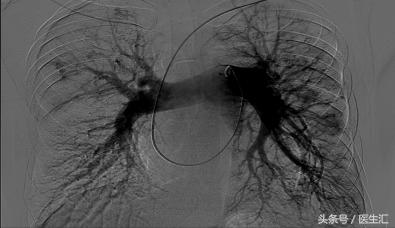

【胸片】

肺动脉造影+右心导管检查

造影所见:肺动脉主干及叶肺动脉明显增粗,双侧肺动脉分支未见明显扭曲,未见明显充盈缺损,可见弥漫性动静脉瘘,远端灌注良好